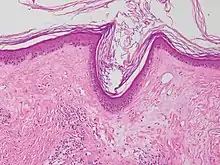

| Lichen nitidus |

|

![]() | ![]() |